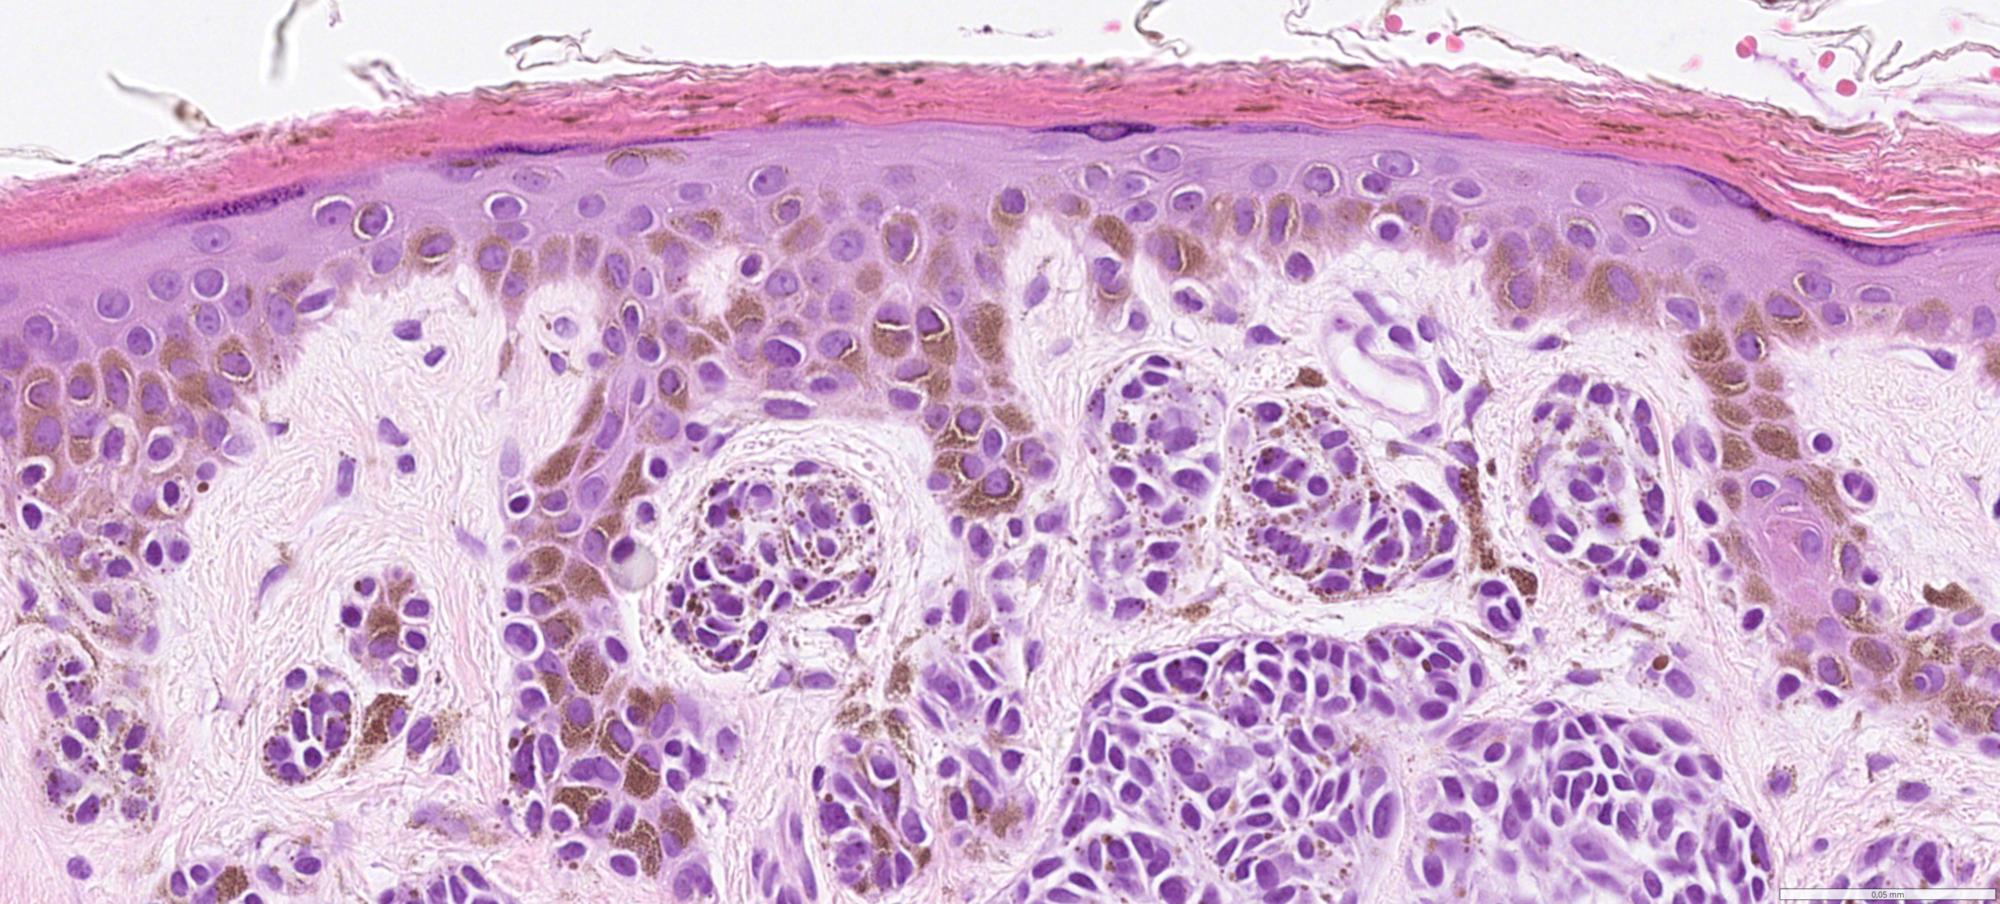

Whole slide pathology images from excision specimens of skin lesions diagnosed at the Department of Pathology at Clinical Department of Pathology at Linkopings University hospital. The dataset contains over 6000 WSIs from from xx excised and punsch biopsies representing a varity of diagnosis categoriesed as malignant melanoma, basal cell carcinom, squamous cell carcinoma and benign diagnosis (eg including melanocytic nevus).

Histopathology

malignant melanoma

basal cell carcinom

squamous cell carcinoma

benign